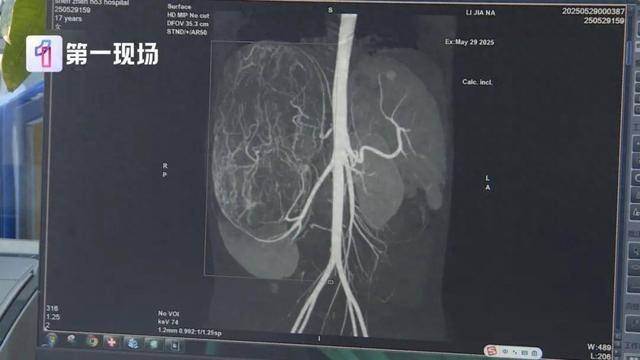

直径长达27厘米

等到了当地医院一检查,CT结果显示,她的右肾有恶性肿瘤伴肝转移可能,家长就立即带着孩子来到深圳求医皇冠信用網在线申请 。

肿瘤已经到了肚脐的下缘,就是后腹直肌外侧,这种情况需安全地把肿瘤切除,不要把肿瘤搞破,是我们首先要考虑的问题皇冠信用網在线申请 。

切除的肿瘤将近5斤重

直径达27厘米

肿瘤切出来后,我们测量了大小有27公分,重量有2.435公斤,非常非常的大皇冠信用網在线申请 。